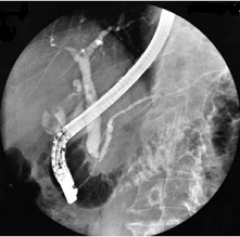

Figura 2: Colangio-pancreatografia Figura 3: Representação do exame

A CPRE é realizada introduzindo-se, pela boca até a segunda porção duodenal, um aparelho flexível com iluminação lateral (duodenoscópio) que permite a introdução de um cateter pelo orifício de abertura desses canais (papila duodenal ou de Vater) a fim de avaliar radiologicamente (figura 2) a anatomia das vias biliares e do ducto de Wirsung, pela administração de contraste radiopaco pelo cateter injetor seguida de radiografias seriadas do abdômen.